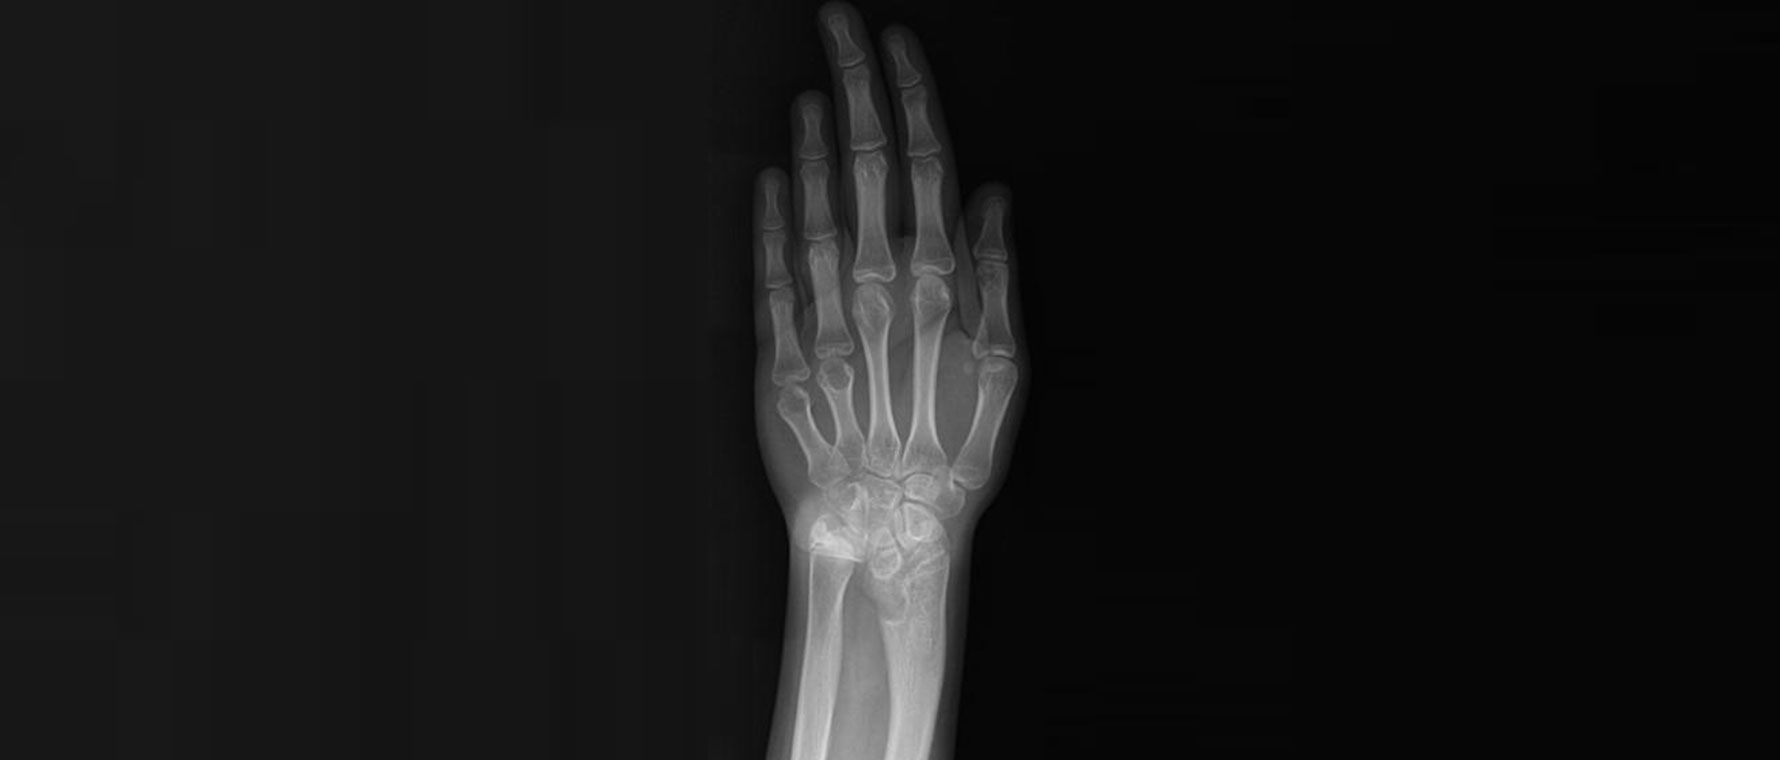

Eksik – Gelişmemiş Başparmak (Hipoplazik Başparmak)

Hipoplazik başparmak, başparmağın doğuştan küçük, zayıf veya işlevsiz olması durumudur. Başparmak, elin kavrama ve tutma fonksiyonu için çok önemlidir. Bu nedenle hipoplazi, çocuğun elini kullanmasını belirgin şekilde zorlaştırabilir. Hafif olgularda başparmak küçüktür ama işlev görürken, ağır olgularda neredeyse yok denecek kadar gelişmemiş olabilir. Tanı muayene ve röntgenle ile konur. Tedavi, başparmağı güçlendirmeye yönelik cerrahileri veya işlevsizse işaret parmağının başparmak haline getirilmesini içerebilir. Amaç, elde güçlü ve fonksiyonel bir kavrama sağlamak ve çocuğun günlük yaşamını kolaylaştırmaktır.